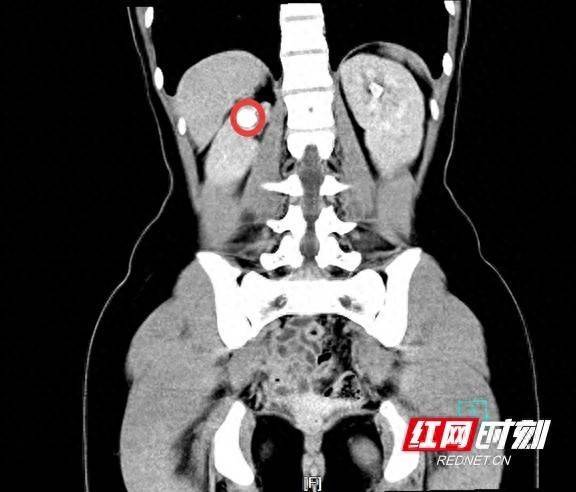

影像资料上可以看到女孩右侧多长了一个肾(红圈内)。

入院完善相关检查发现,小悦右侧有2个肾盂和2根输尿管,其中一根输尿管的开口位于阴道壁,绕过了膀胱这个“蓄水池”,同时也避开了尿道“阀门”的管控,导致“水龙头”关不住,长期漏尿。